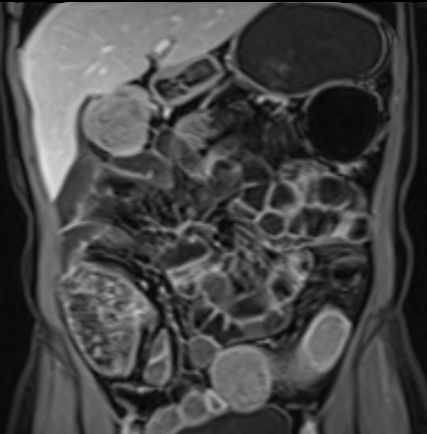

Bệnh nhân nữ 48 tuổi, đang điều trị bằng thuốc kháng TNF, được chỉ định nội soi đại tràng.

Phát hiện hẹp lòng ruột ở đại tràng sigma, không thể vượt qua được khi nội soi.

MR-enterography được thực hiện để đánh giá mức độ lan rộng của chỗ hẹp.

Cuộn qua các hình ảnh.

Ruột non bình thường, nhưng ghi nhận các đoạn hẹp ở đại tràng xuống và đại tràng ngang.

Cả hai đoạn hẹp đều có thành ruột dày đến 8 mm và ngấm thuốc rõ rệt theo kiểu niêm mạc ở đại tràng xuống và kiểu phân lớp ở đại tràng ngang.

Giãn ruột trước chỗ hẹp được ghi nhận ở cả hai đoạn.

Do các chỗ hẹp này không hiện diện khi nội soi đại tràng trước khi điều trị kháng TNF, nhiều khả năng chúng đã hình thành trong quá trình điều trị.

Do đó, quyết định phẫu thuật cắt đại tràng gần toàn bộ với miệng nối hồi-sigma đã được đưa ra.